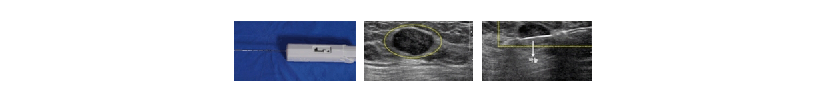

2 중심부 바늘 조직 검사(=코어 생검술)

중심부 바늘 조직 검사는 세침 흡인 세포 검사 시 사용하는 바늘보다 더 굵은 바늘을 사용하여 조직을 얻어내는 방법으로 세침 흡인 세포 검사에 비해 그 정확도가 더 높습니다.

따라서 요즘에는 초음파 유도하 중심부 바늘 조직 검사가 유방 조직 검사의 기준으로 여겨지고 있습니다.시술 방법

A 피부 소독->국소 마취->초음파 유도하에 병변에 특수 바늘 삽입-> 3~4회 반복하여 조직 샘플 채취-> 병리 전문의의 현미경 관찰로 암세포 유무 판단->1주일 후 진단 확정

B 시간은 10분 정도 소요되며, 국소 마취 후 시술합니다.

C 통증은 유방 촬영보다 덜한 정도로 심한 편이 아닙니다. 편안하게 진료 받으십시오.리앤아이 유방 센터만의 노하우

중심부 바늘 조직 검사를 할 때는 약간의 피부절개를 하는 것이 일반적이지만 저희 리앤아이 유방 센터에서는 풍부한 임상 경험을 바탕으로 피부절개를 하지 않고 검사를 하기 때문에 시술 후 흉터가 전혀 남지 않는 장점이 있습니다.